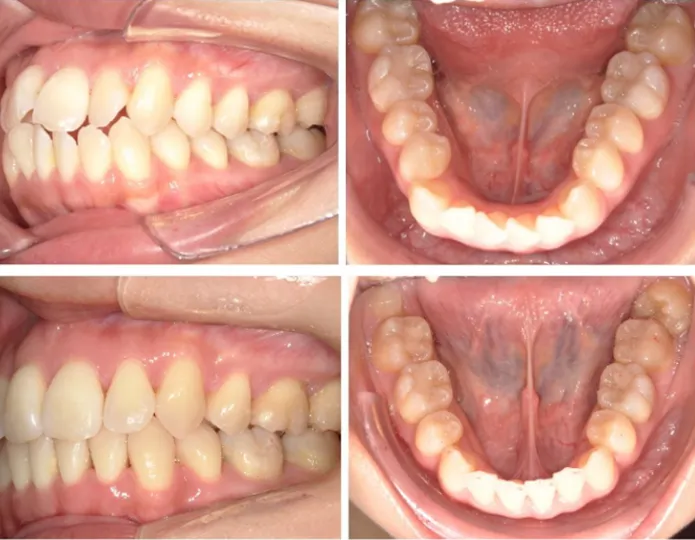

| 叢生におけるハーフリンガル矯正治療の症例 | |

| 主訴 | 歯磨きが難しい、虫歯になりやすい、歯列のガタガタ、口元の突出 |

| 診断 | 叢生を伴う不正咬合、正中の偏位、上下唇の突出 |

| 年齢 | 女性・20代 |

| 使用装置 | ハーフリンガル矯正(上顎が舌側矯正、下顎が表側矯正) |

| 抜歯 | あり |

| 治療期間 | 約2年 |

| 治療費 | 1,150,000円(税込) (検査費、診断費、通院毎の調整費は別途) |

| リスク・副作用 | 歯根吸収、歯肉退縮、カリエス(虫歯)、歯周病、後戻り等の可能性があります。 |